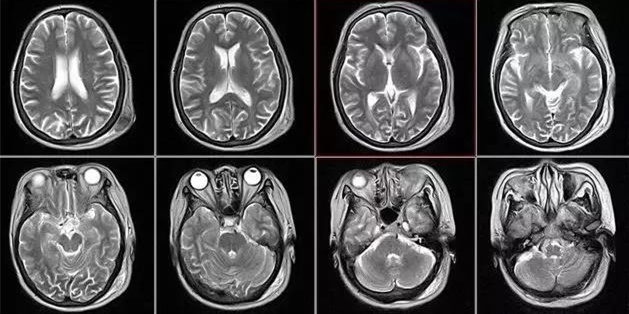

核磁共振仪使用较强大的磁场,使人体中所有水分子磁场的磁力线方向一致,这时磁共振机的磁场突然消失,身体中水分子的磁力线方向,突然恢复到原来随意排列的状态。简单说,就相当于用手摇一摇,让水分子振动起来,再平静下来,感受一下里面的振动。所以,核磁共振也被戏说为是摇摇看的检查。

颈椎病、腰椎间盘突出等椎间盘疾病需要观察椎间盘与相应的神经根,要想更好观察这些软组织,最优选择就是核磁。同样,对于关节、肌肉、脂肪组织检查,核磁也是首选。

用CT可检查冠状动脉,但冠脉CT检查辐射量较大,不适合作为常规体检。核磁虽无电磁辐射,但对冠状动脉的观察不及CT。心脏核磁则是评价心脏结构和功能的“金标准”。(肝胆相照-肝胆病在线公共服务平台www.igandan.com)